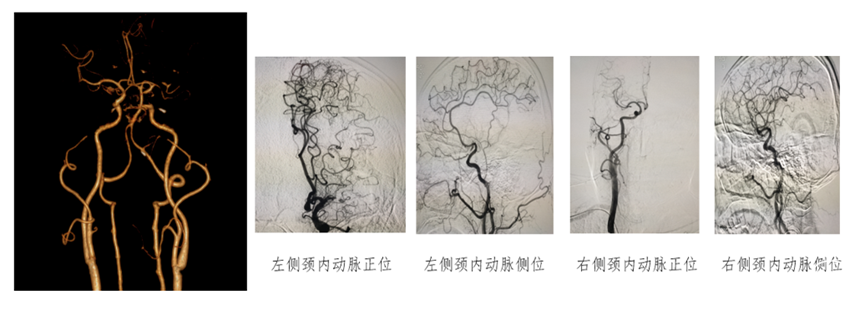

经绕动脉完成的颈内动脉介入通路:

1、经绕动脉完成的左侧颈内动脉介入通路建立示意图

桡动脉入路治疗CAS--左侧颈动脉(西蒙导管导引)

关键技术:无交换 导引导管到位技术(外管+西蒙导管)

2、经绕动脉完成的牛型颈内动脉介入通路建立示意图

经绕动脉完成牛型颈内动脉介入通路建立示意图

3、经绕动脉完成右侧颈内动脉介入通路建立示意图

桡动脉入路治疗CAS--右侧颈动脉

关键技术:无交换 导引导管到位技术(外管+猪尾造影导管)

经绕动脉左侧颈内动脉支架:

0.035in泥鳅导丝携带猪尾导管或西蒙导管超选左侧颈总动脉,困难在于弓内无血管壁支撑,导管容易下掉,必要时将加硬泥鳅导丝到达颈外动脉支撑6F导引导管或6F长鞘到达颈总动脉远端建立通路,支架通过弯道或推挤释放时容易出现下掉,注意调节导管。

经绕动脉右侧颈内动脉支架:

0.035in泥鳅导丝携带猪尾导管或西蒙导管超选右侧颈总动脉,困难在于血管成角,导管容易打折,必要时将泥鳅导丝或微导丝支撑到达颈外动脉,支撑6F导引导管、DA远端通路导管或6F长鞘到达颈总动脉远端建立通路,西蒙在无名动脉容易拉入颈总动脉,缓慢回拉导管的同时注意调节释放导管成祥,减轻血管刺激和打折。

左侧颈动脉重度狭窄经桡动脉介入治疗

Ⅲ型弓,经股动脉难以到位。

穿刺右侧桡动脉,置入6F桡动脉鞘,上5F猪尾造影导管,但很不巧,碰上了桡动脉环,但环不大,将导丝送到动脉环,跟进导管,再将导丝走远,动脉环就变直了,继续跟进导管。

1、通路建立

将猪尾造影导管送入主动脉弓,将260cm泥鳅导丝送入到降主动脉,撤出造影导管,沿导丝送入西蒙导管+6F导引导管组合,尝试将西蒙导管送入到降主动脉成绊未能成功,遂将头端较软的导引导管先送入到降主动脉,再送入西蒙导管,后撤导引导管,西蒙导管成绊,再选入左侧颈动脉,跟进导引导管,回撤西蒙导管,这时导引导管不稳,有下滑的趋势,遂先继续送入导引导管,再回撤西蒙导管,通路建立成功。

2、沿导引导管送入保护装置,释放后,尚导丝送入4-30mm球囊,予以6atm压力扩张,撤出球囊,造影示狭窄。

3、最关键的时刻来了,撤出球囊,沿导引导管送入8-40支架,在支架要过主动脉弓时,导管不稳,有下滑的感觉,远端的保护装置也往下移位,需要进行调整,将保护装置再往上送,缓慢的跟进导管到狭窄处,这样导管的支撑力就够了,再缓慢的送入支架,终于支架安全到位。

支架准确定位后,缓慢的后退导引导管,再缓慢的释放支架,在释放的时候还是有一点张力,释放较困难,需要给点力,支架释放完后,再沿支架输送器往上送导管,造影示有残余狭窄,予以PTA 5-30球囊扩张。

4、球囊扩张后,尚球囊送入导引导管通过支架至C1段远端,将保护装置回收。

本例患者为Ⅲ型主动脉弓,无名动脉与左侧颈总动脉几乎平行、左侧颈总动脉与主动脉弓也是很小的锐角,无论是从上肢入路还是下肢入路都很难建立通路;

本例患者存在经桡动脉入路的诸多障碍,但因患者的强烈需求,最终还是尝试经右侧桡动脉入路进行手术,最终顺利完成,道虽迁,行则将至,面对困难,需要面对,勇于尝试,才能不断进步,但术前也需要做好各种紧急预案,术中小心操作,将风险控制在最小程度。